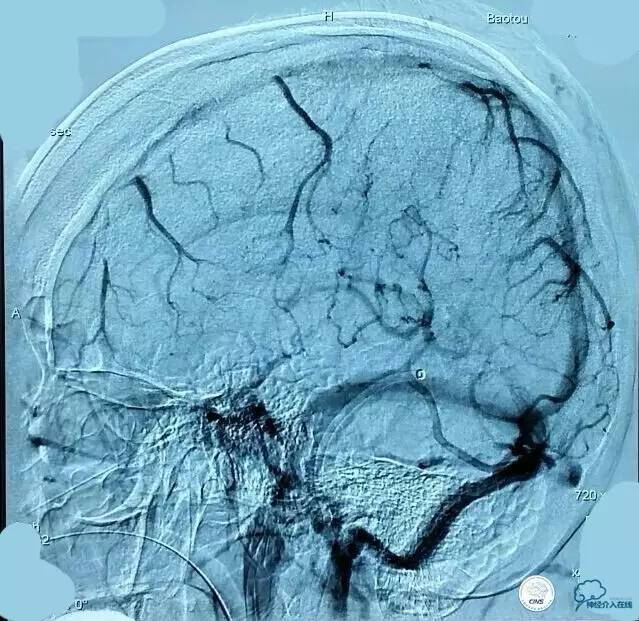

▼第三次取栓后造影,窦通畅,下矢状窦显影延迟,说明上矢状窦通畅了。

▼正位:

静脉窦血栓入路比动脉路径要困难的多,可以采用的手段以往主要是接触性溶栓、球囊扩张,手术往往要耗费大量的时间。随着介入器材的不断进步,我们配合中间导管、可回收支架取栓技术、接触性溶栓技术,大大提高了效率,提高了开通率,明显缩短手术时间。